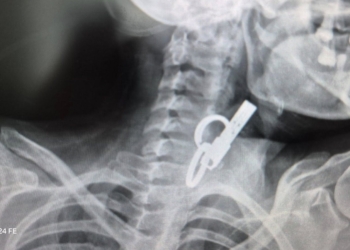

Позначка: ендоскопія